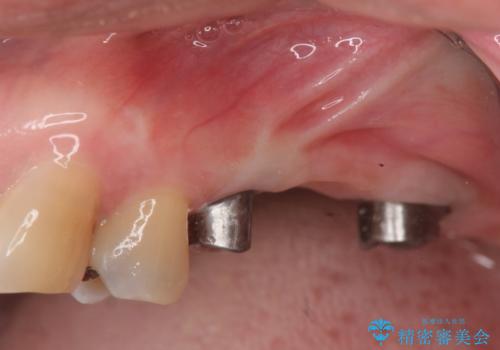

- 110万円(インプラント×2・チタンカスタムアバットメント×2・ジルコニアクラウン×3・仮歯×3)費用は治療当時の料金となります